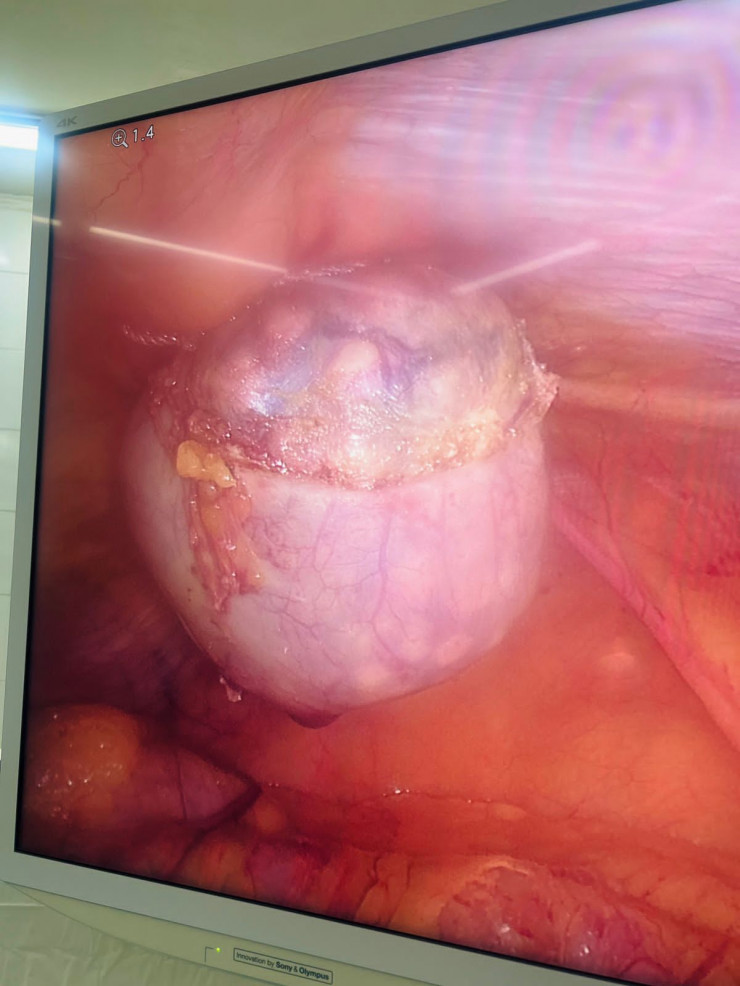

62-летняя женщина поступила в городскую клиническую больницу №7 города Алматы в экстренном порядке с жалобами на боли в правом подреберье, тошноту, рвоту, сухость во рту. После обследования больной был выставлен диагноз: "Желчекаменная болезнь. Острый калькулезный холецистит". На следующий день ей была проведена лапароскопическая операция.

После удаления желчного пузыря из него было извлечено 1735 конкрементов диаметром от нескольких миллиметров до 1,5 сантиметра.

Специалисты отмечают, что желтый цвет камней обусловлен повышенным содержанием холестерина. Фото предоставлено пресс-службой ГКБ №7 города Алматы

Специалисты отмечают, что желтый цвет камней обусловлен повышенным содержанием холестерина.